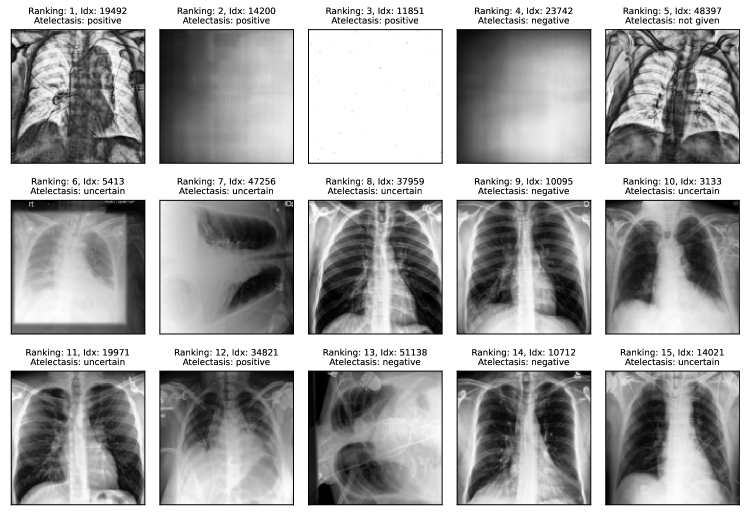

Comparison with human annotators. We evaluate SelfClean rankings based on human annotations across two medical and two common vision benchmarks as described in appendix I. The evaluation reveals that images ranked by SelfClean as the most likely to contain data quality issues are also identified by human experts as problematic significantly more often than random images. As shown in table 8, we find 95% significant differences in nine of twelve evaluations for comparing the lowest 50 ranked images to a random selection and six of ten evaluations for comparing images ranked 1-25 to images ranked 26-50. Two cases in the second comparison are excluded because too many positive samples give undefined metrics. Results indicate that the proposed ranking, to a large degree, coincides with human understanding of these three noise types. Therefore using SelfClean can increase efficiency when analyzing and fixing data quality issues.